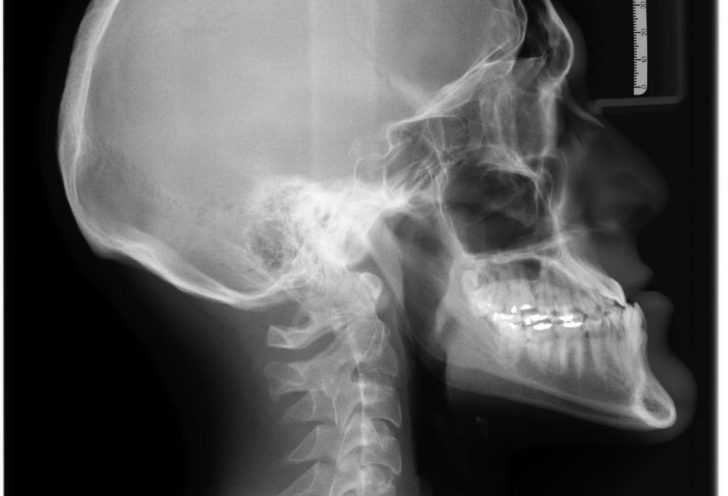

En røntgenundersøgelse er en billeddiagnostisk teknik, der anvender røntgenstråler til at skabe billeder af indre strukturer i kroppen. Røntgenstråler kan trænge igennem forskellige væv, men absorberes i forskellig grad. Knogler, som indeholder calcium, absorberer røntgenstråler effektivt og fremtræder derfor tydeligt på billederne. Blødere væv, som muskler og fedt, absorberer færre stråler og fremstår derfor mindre synlige.

Den mest kendte type røntgenundersøgelse er den klassiske røntgen. Denne type undersøgelse bruges ofte til at diagnosticere knoglebrud, artritis, tandproblemer og andre tilstande, hvor knogler spiller en central rolle. En stor fordel ved Klassisk røntgen er dens evne til hurtigt at give resultater, hvilket er afgørende i akutte situationer.